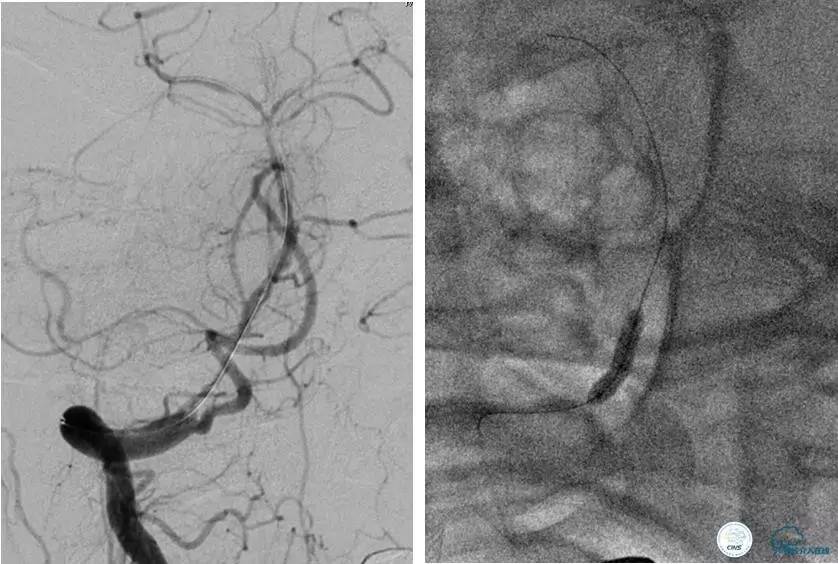

患者:49岁男性,左侧偏瘫1个月,药物治疗、康复训练效果不好,转我院,肌力0~1级。

core-clilnical明显不匹配,是介入开通的合适患者。

造影评价血管、判断闭塞段,微导丝小心穿过闭塞段,微导管造影,交换技术,球囊扩张,Enterprise支架。在后扩张时导丝刺破M3段血管,蛛网膜下腔出血(SAH)。

微导管进入破裂血管,栓塞弹簧圈1枚,出血停止,结束手术。继续双抗,术后2天肌力2级,神经功能恢复明显加快。

术后即刻和6天后CT,患者无明显临床症状。

半年后复查造影,无支架内再狭窄,可见弹簧圈,患者恢复至自己柱杖行走。